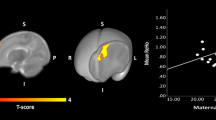

A positive association was observed between MBMI and the mean MD in the right hippocampus (beta = 4.084 ± 1.341 (×10−6), t = 3.045, p = 0.00287) (see Fig. 1). The positive association between MBMI and the left hippocampus mean MD (beta = 3.670 ± 1.475 (×10−6), t = 2.489, p = 0.0142) did not survive the FDR correction. There were no associations between MBMI and amygdala MD (right: beta = 1.190 ± 1.037 (×10−6), t = 1.147, p = 0.254; left: beta = 6.683 ± 4.795 (×10−7), t = −0.868, p = 0.387).

Positive associations between maternal pre-pregnancy body mass index and infant hippocampus mean diffusivity analyzed with a voxel-wise permutation analysis adjusted for infant sex and age from birth in days presented on a a T2 weighted average whole-brain image of the study population and on b a 3D rendering of segmented right (up) and left (down) hippocampi. Voxels that are significant (p < 0.05) after threshold-free cluster enhancement correction for multiple comparisons are presented in the figure. The color bar represents 1 − p values. a and b are in neurological convention (right hippocampus top and left hippocampus bottom). Same associations presented with a scatterplot (c) for left hippocampus (left) and right hippocampus (right).

Voxelwise permutation tests, adjusted for infant’s sex and age from birth in days, yielded significant voxels in the posterior right hippocampus and anterior left hippocampus (see Fig. 1). No significant voxels were detected in the amygdalae. None of the tests yielded sex differences.